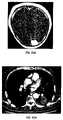

Case 1. A 59 year-old male patient suffered a stroke in the left basal ganglia. SPECT99mTc-EC-MN identified the lesions at one hour post-injection (FIG. 28), which corresponds to MRI T1 weighted image (FIG. 29).

Case 2. A 73 year old male patient suffered a stroke in the left medium cerebral artery (MCA) territory. SPECT99mTc-EC-MN was obtained atday 1 and day 12 (FIGS. 30 and 31) at one hour post-injection. The lesions showed significant increased uptake atday 12. CT showed extensive cerebral hemorrhage in the lesions. No marked difference was observed betweendays 1 and 12 (FIGS. 32 and 33). The findings indicate that the patient symptoms improved due to the tissue viability (from anoxia to hypoxia). SPECT99mTc-EC-MN provides functional information which is better than CT images.

Case 3. A 72 year old male patient suffered a stroke in the right MCA and PCA area SPECT99mTc-EC-MN identified the lesions at one hour post-injection (FIG. 34). CT exaggerates the lesion size. (FIG. 35).